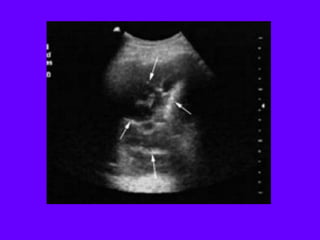

IVC Sonography

IVC Longitudinal

1 Place probe longitudinally in right anterior

mid-axillary line with marker towards the head

2 Look for IVC running longitudinally

adjacent to liver crossing the diaphragm.

3 Track superiorly until it enters right atrium